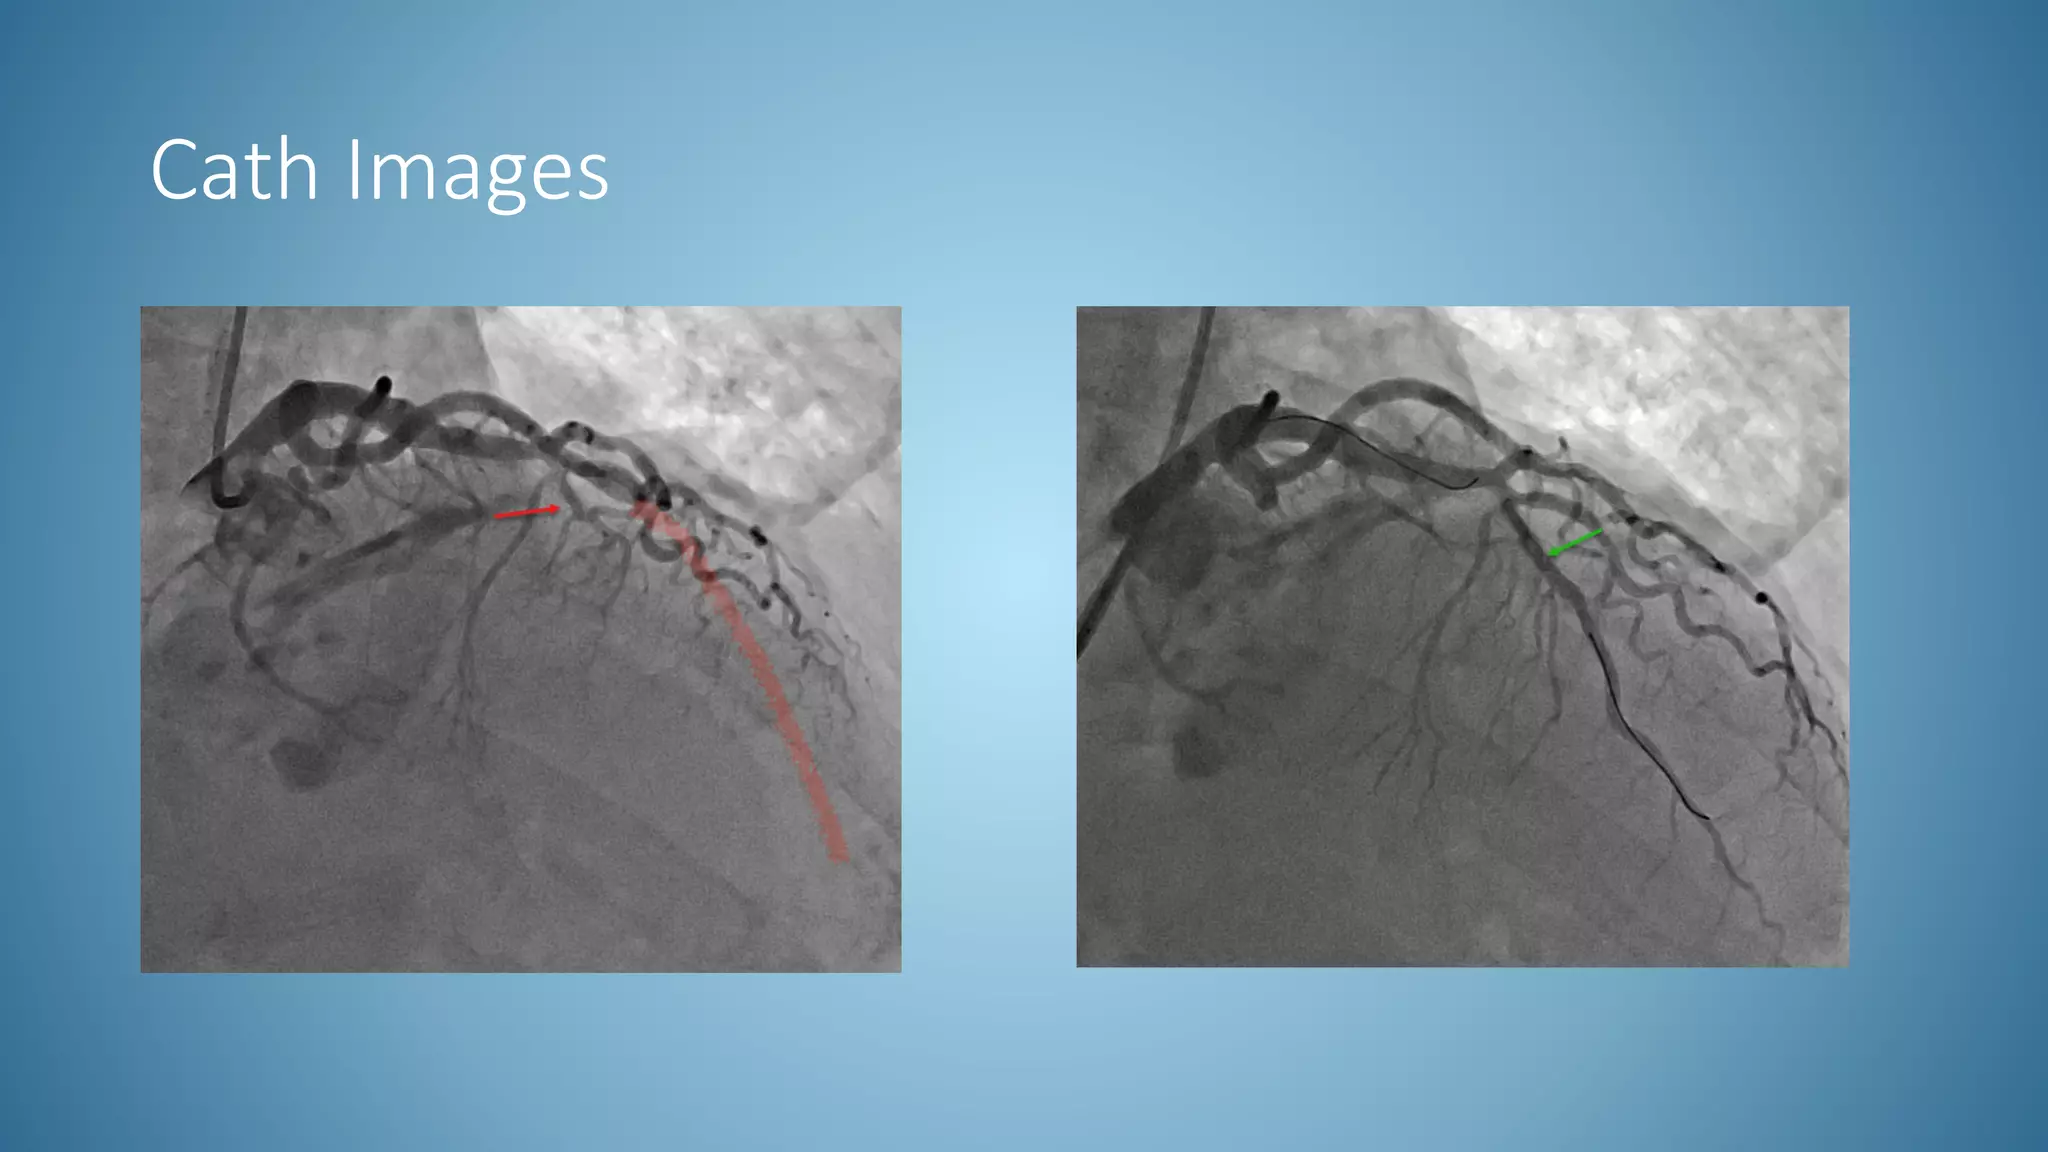

Cath Images

• STEMI activated by Emergency Room (30 min after arrival)

• Initial Trop 0.23

• Elevated LDL at 249, there is a high chance for familial hypercholesteremia

• Echo performed resulting with a mild ischemic cardiomyopathy significant for

an EF of 40% with LAD wall motion abnormalities

• 3 day admission stay

• EDUCATION POINTS

• Less likely in younger age group, but bigger opportunity to make a difference